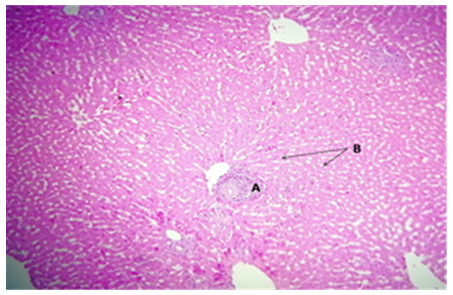

3.6 Microscopic analysis of liver tissue

The liver tissue's microscopic examination exposed evidence of hemorrhage and hemolysis, alongside significant inflammatory cell infiltration around the portal vein. A notable presence of macrophages (Kupffer cells) within the sinusoids was also observed. Moreover [33], fatty necrosis was prevalent in a majority of hepatocytes, highlighting the protective and reparative roles of chitosan against liver damage induced by stress factors and possibly by the metabolic disturbances associated with fungal infections, as shown in Figures 4-9, which starkly contrast the findings in the control group.

Figure 4. The histological slice of the chitosan-treated liver revealed: A) hemorrhage within parenchyma as well as B) hemolysis